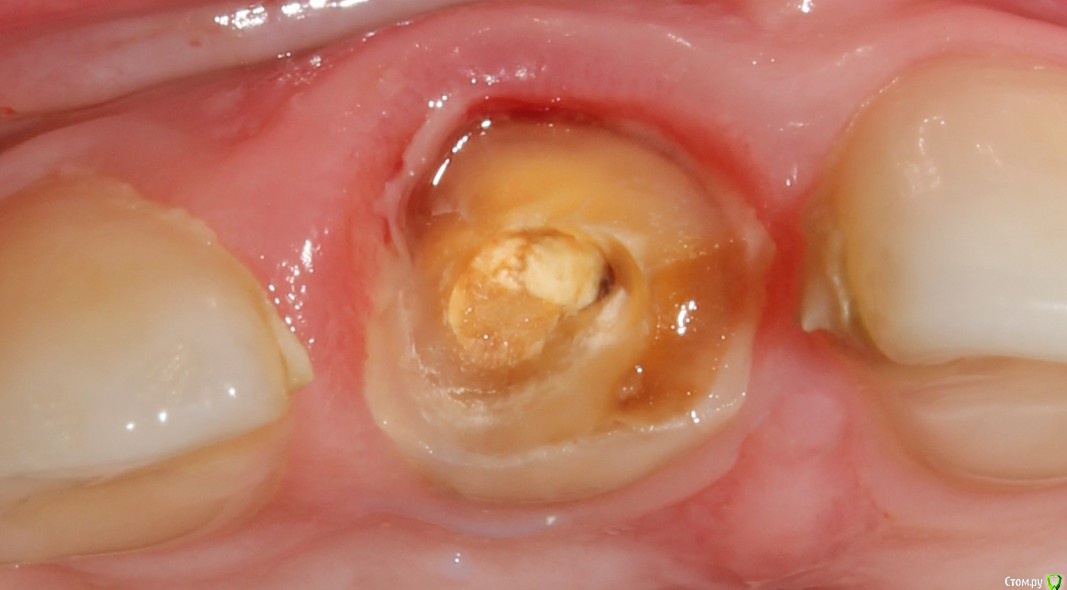

Рустам Опубликовано 4 ноября, 2016 Поделиться Опубликовано 4 ноября, 2016 Добрый вечер коллеги! Вчера обратилась пациентка (19 лет) с жалобой на подвижность коронки 1.1 зуба.Коронку убрал, скол достаточно глубоко (2-3мм ниже уровня десны), в зоне БШ. Удлинение во фронте не вариант на мой взгляд. Феррул не получить. Имплантолог ввиду возраста в имплантации отказывает.Пока сделал временный зуб на униметрике. КТ пока не делали. Записал на повторную консультацию. Как бы вы поступили в данной ситуации Ссылка на комментарий

229KAMA Опубликовано 4 ноября, 2016 Поделиться Опубликовано 4 ноября, 2016 Возможно вы не так выразились но коронки ни на одном из представленных снимков я неувидел.Теперь чтобы сделал я , учитывая гигиену по снимкам и количество зубов и качество пломб предположу как и уменя в госе я бы поработал "спасателем" как обычно за неимением финансовой возможности у больного , а может и особого желания заниматься зубами.1-подрезалбы десну по вестибулярке.2-времен.востан.коронк. часть зуба через анкерный штифт.(хорошо его зафиксир)чтобы попробовать немного вытянуть коронарно.(потреб времен.конечно и за свой счет ну хотябы частично.)3-после того как зуб перем корон.поработать с десной (может и с биологической шириной) по вестибулярке для того чтобы спрогнозировать минималный ферул. Ну тоже часть финанс нагр на мне.4-дальше если ферул получил то ВКВ и далее как обычно коронк.Да знаю нормальный врач сразу мне СКАЖЕТ что все это мартышкин труд надо ВСЕ как положенно , удалить может одномоментно винт и т.д.Но мне часто приходиться пахожие ситуации разруливать и зная как правильно НАДО , по обстоятельства разным приходиться становиться "спасателем" всегда заранее поциентам обьясняю что это не по протоколу. Только после этого пытаюсь оттянуть смертный приговор зуба. Некоторые возврашаются накопив средства чобы все сделать правильно и меня это радует , что кто то правильно понял мою информацию как надо правильно. Както так действую. 1 Ссылка на комментарий

Рустам Опубликовано 6 ноября, 2016 Автор Поделиться Опубликовано 6 ноября, 2016 Коллеги, как считаете возможен такой вариант, закрыть корень зуба СИЦем, коронку 11 сделать либо на глашпане, либо мериленд приклеить на пару лет, потом в 21-22 года удаление корня с одномоментной имплантацией и немедленной нагрузкой. Ссылка на комментарий

DmitrySH Опубликовано 6 ноября, 2016 Поделиться Опубликовано 6 ноября, 2016 Коллеги, как считаете возможен такой вариант, закрыть корень зуба СИЦем, коронку 11 сделать либо на глашпане, либо мериленд приклеить на пару лет, потом в 21-22 года удаление корня с одномоментной имплантацией и немедленной нагрузкой.Не вижу смысла.Лучше поставить индивидуализированный СВШ, композитный билдап и качественная временная коронка. Далее или ортодонтическая экструзия до желаемого уровня или одномоментная имплантация через пару лет. 2 Ссылка на комментарий